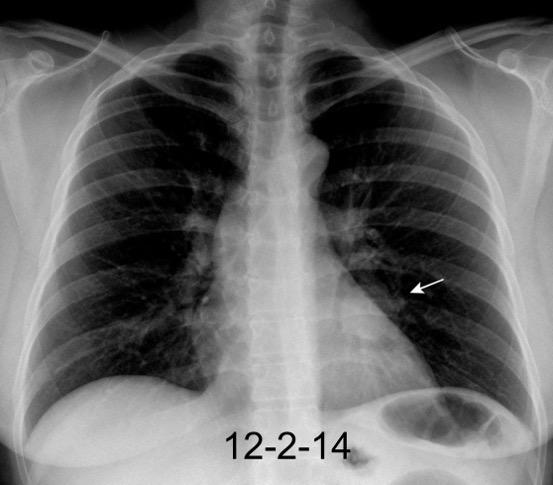

30 años

Borramiento de la banda PARA-aórtica por AdenoCa. de LII, no visible en 2005

Colapso de LII. TC: secreciones bronquiales.

Endoscopia tapón mucopurulento extraído